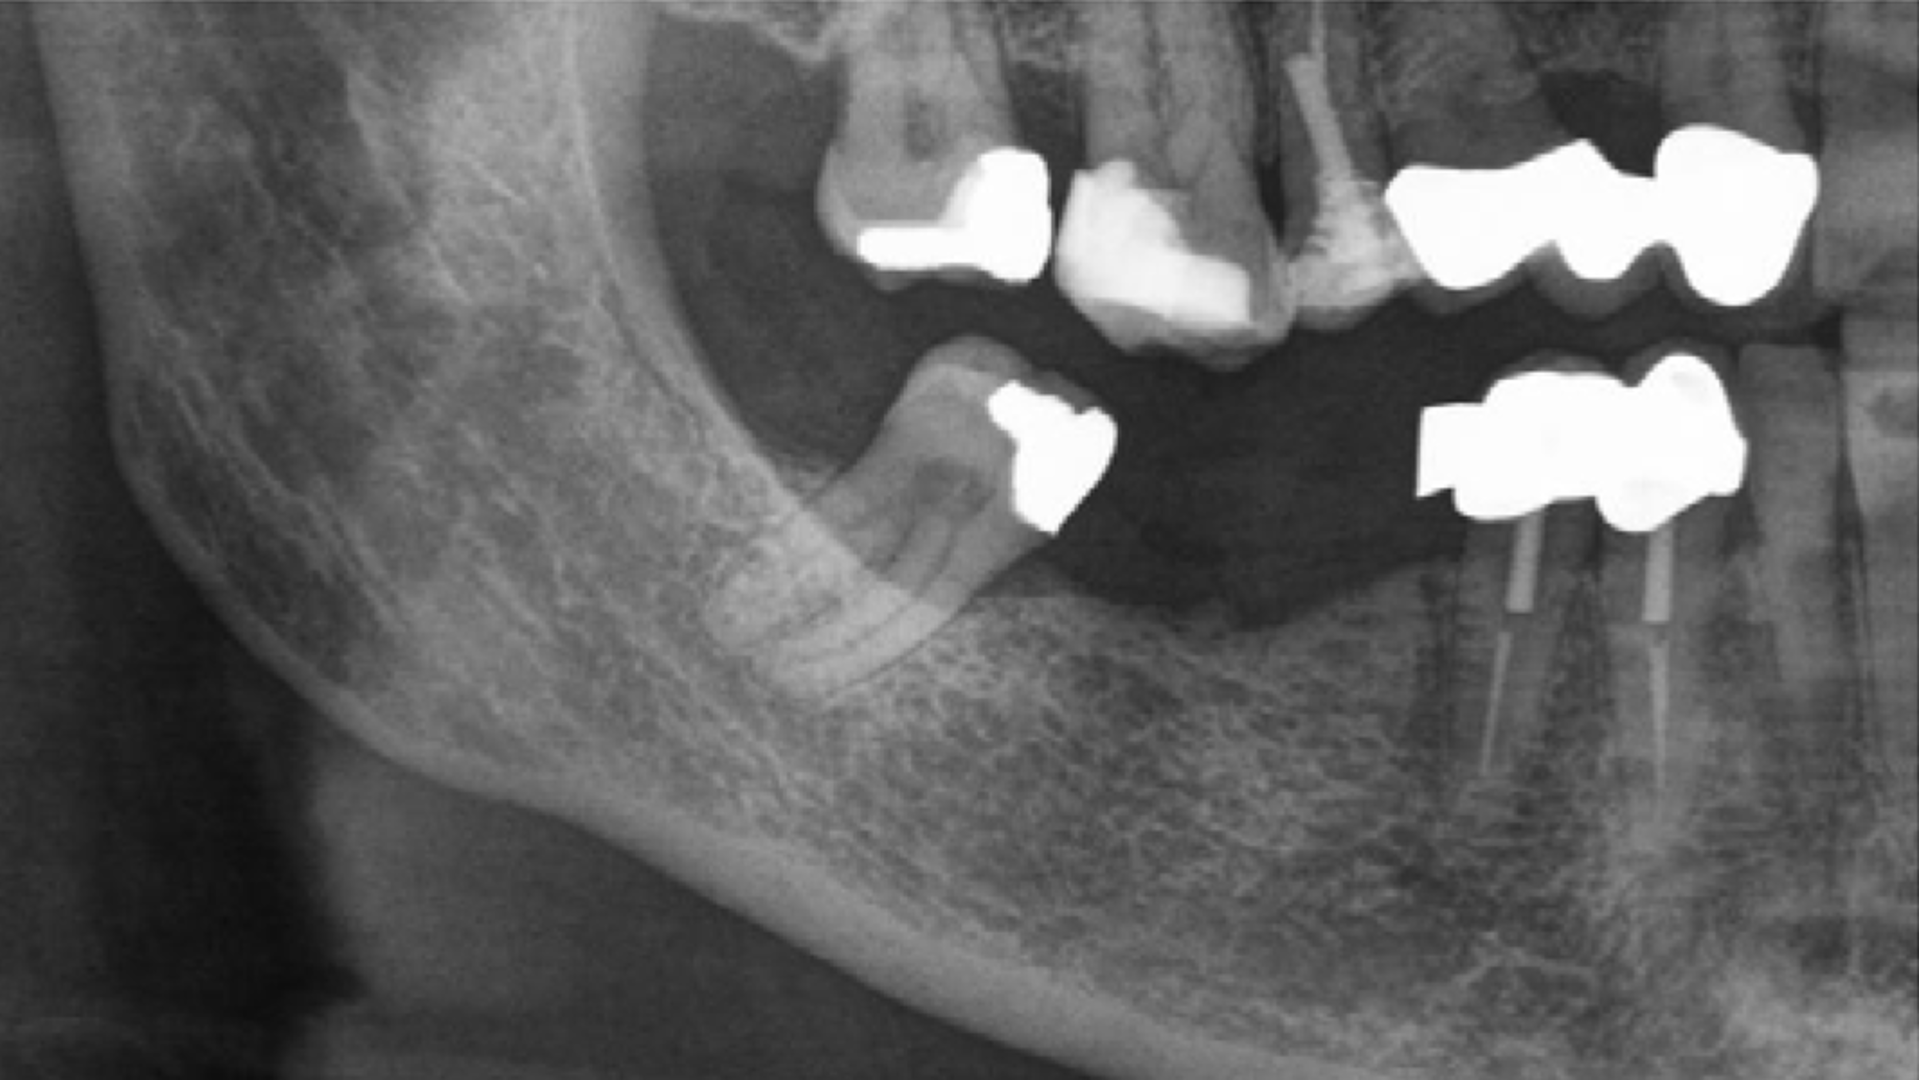

3 Kloss et al. Clin Case Rep. 2020, 8(5):886-893.

5 Kloss et al. Clin Oral Implants Res. 2018, 29, 1163.

9 Barone et al. Int J Periodontics Restorative Dent. 2024;44(6):685-696.

10 Kloss et al. Int J Implant Dent. 2024. 10(1):42.